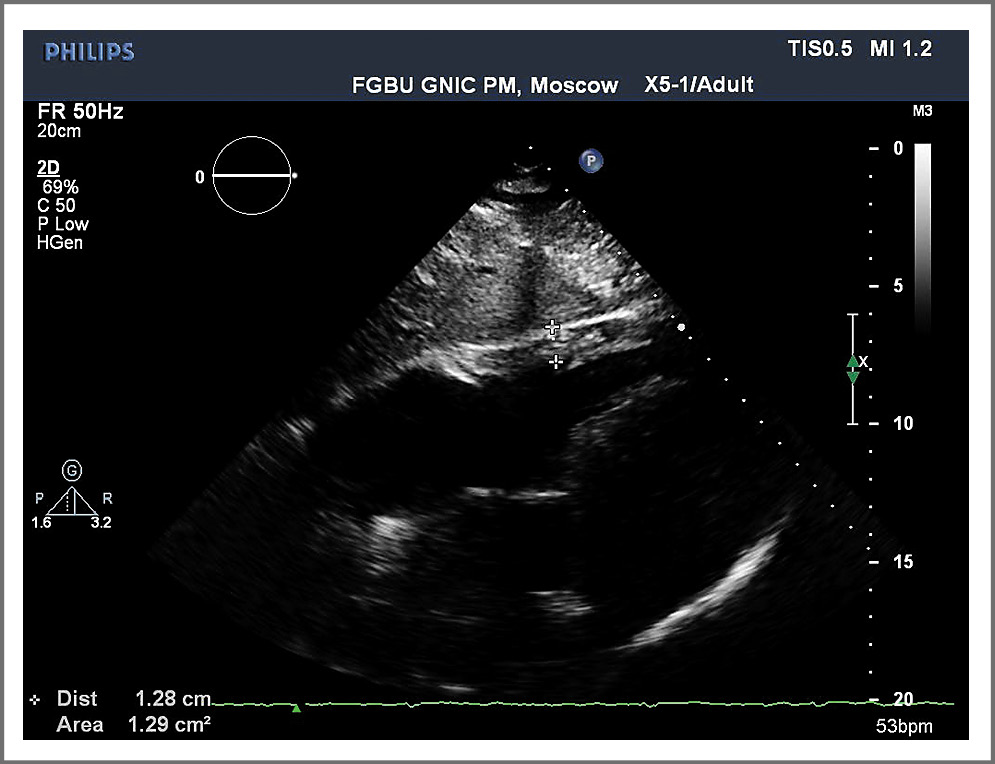

При измерении из парастернального доступа в позиции по длинной оси ЛЖ необходимо оценить соотношение поперечного размера аорты и ЛП, толщину межжелудочковой перегородки, конечно-диастолический и конечно-систолический размеры ЛЖ, толщину задней стенки (рис. 2). Измерение толщины межжелудочковой перегородки может быть затруднено из-за таких структур ПЖ, как трабекулы, наджелудочковый гребень и модераторный пучок. Толщина стенки может быть проверена дополнительно в парастернальной позиции по короткой оси (рис. 3).

Рис. 2. Оценка структур из парастернального доступа в позиции по длинной оси ЛЖ.